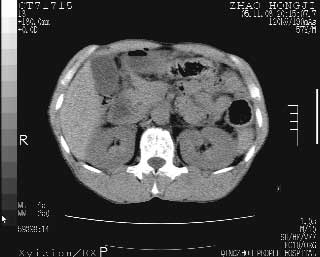

临床资料:男性,57岁,上腹部疼痛并5天,突然加重并延及全腹伴恶心5小时入院。胰淀粉酶化验在正常范围。检查:腹肌紧张,全腹压痛、反跳痛,尤以右上腹部为著。肠鸣音减低。血常规:wbc14.6x10/9, n:11.3x10/9 ,血压:135/90mmhg. 胸部透视:腹部肠腔轻度张气,未见其它异常改变。

胰腺形态规则,胰周脂肪间隙清晰,结合临床可排除急性胰腺炎

从图提示我同意空腔脏器穿孔的诊断,来源肠道{由于病程较短,故没能见到肠系膜聚局的征象}。

肝缘见少许气体,胰尾部见少许气体包饶(蓝色圈),12指肠上部或球部邻近胆囊周边也可见少许气体影(黄色圈),并忖托出胆囊壁,12指肠远段肠道内未见明显气体(白色箭)。

消化道穿孔。12指肠球部周和胰周积气考虑12指肠穿孔可能性大。

入院3小时后行剖腹探查术,见腹腔内大量脓性混浊液约1000ml,十二指肠球部溃疡穿孔,溃疡面约2.5x2cm,穿孔直径约0.6cm。胃内容物外益,周围组织炎性水肿明显。行十二指肠穿孔修补术。术后诊断:

1、十二指肠溃疡穿孔

2、弥漫性腹膜炎

对于少量的腹腔游离气体,ct检查较普通透视有绝对的优势,它不仅可以看到肝脏前上缘的气体,而且还能够看到小网膜区的游离气体。从而可以肯定诊断。各位分析战友的很好,感谢大家的参入!